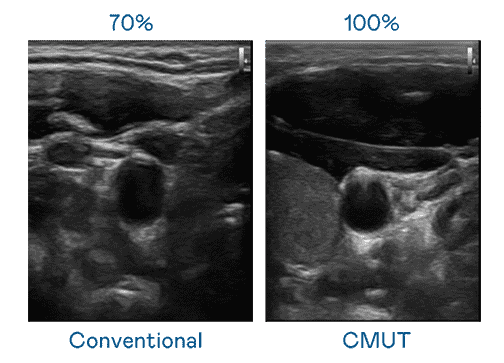

CMUT 技术是一种用电容式微机电元件来产生超音波讯号的技术。。。与传统 PZT 压电式技术相比,,,,CMUT 频宽增加 30%,,,,更宽频的超音波讯号让影像解析度大幅提升,,,是实现高影像品质医疗超音波扫描、、促进精准医疗发展的关键技术。。。。

大频宽带来超清晰影像

超音波影像的解析度高低,,,首先取决于探头能发出的讯号频宽。。。。冰球突破 CMUT 可提供高清晰的超音波讯号,,,,提供高频宽、、、高灵敏度、、、影像纹理细节更高的超音波影像,,,,协助医护人员缩短影像判读时间及利用精准的医疗影像进行诊断。。。。